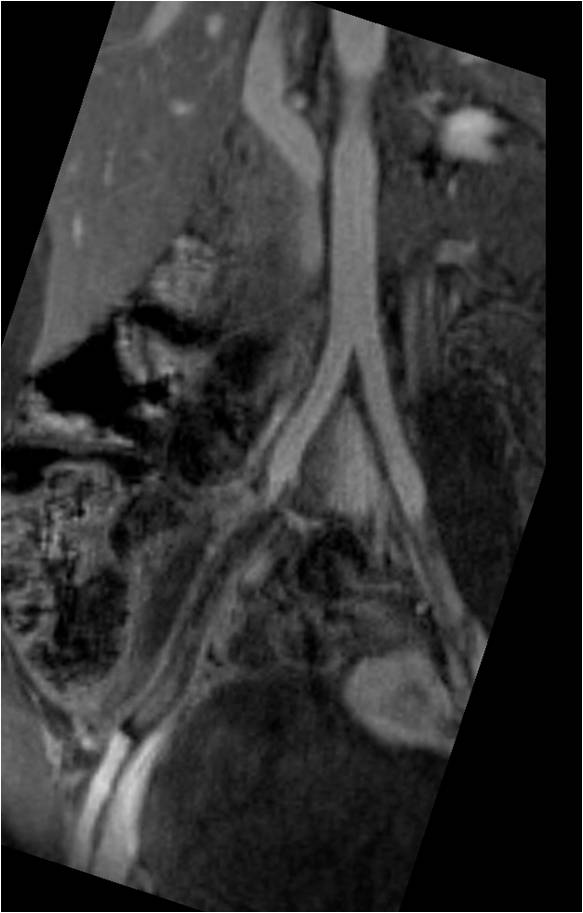

Popliteal artery entrapment syndrome

There are various situations in which the popliteal artery is compressed by muscle fibers crossing over it. This results in popliteal artery entrapment syndrome. The compression may result in leg pain that is very similar to intermittent claudication from atherosclerotic peripheral artery disease. The main difference is that popliteal artery entrapment occurs in young, often healthy, individuals. The typical story is of a young athlete who develops calf pain while exercising. If left untreated, the popliteal artery accumulates damage and eventually may thrombose. This can result in acute limb ischemia. If properly diagnosed, surgical treatment can serve to relieve the compression.